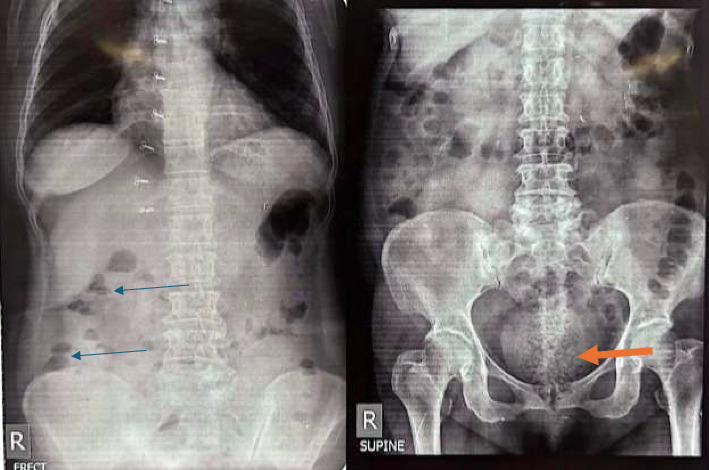

牛黄是一种罕见的胃肠道肿块,由不易消化的物质组成,通常在胃中发现,但有时发生在更远的部位。直肠种子牛黄特别罕见,表现为非特异性胃肠道疾病,容易使诊断困难并延误适当的治疗。我们描述了一个病例68岁的女性表现为急性便秘,压痛的直肠,和直肠出血。病人最近曾食用约100克葵花籽。腹部检查及影像学显示直肠梗阻。直肠灌肠后,患者每条直肠排出一团状的葵花籽,这与直肠种子牛黄相一致。保守治疗:使用大便软化剂、抗生素、软膏和坐浴。这个病例是惊人的,因为它说明了直肠种子牛黄作为一种罕见但可逆的急性便秘的原因的临床意义。诊断需要强烈的怀疑、细致的饮食史和重点检查。早期诊断和保守治疗可以预防并发症,使侵入性诊断不必要的使用。

Bezoars are rare gastrointestinal masses composed of indigestible substances, typically found in the stomach but at times occurring at more distal locations. Rectal seed bezoars are particularly unusual and manifest with nonspecific gastrointestinal complaints, predisposing to making the diagnosis difficult and delaying appropriate therapy. We describe a case of a 68-year-old female presenting with acute constipation, tenderness of the rectum, and per-rectal bleeding. The patient had a history of recent consumption of approximately 100 g of sunflower seeds. Examination and imaging of the abdomen revealed findings of obstruction at the rectum. Following the rectal enema, the patient passed a clumped mass of sunflower seeds per rectum, which is consistent with a rectal seed bezoar. She was treated conservatively with stool softeners, antibiotics, ointments, and sitz baths. This case is striking because it illustrates the clinical significance of rectal seed bezoars as a rare but reversible cause of acute constipation. Strong suspicion, meticulous dietary history, and focused examination are needed for diagnosis. Early diagnosis and conservative management can prevent complications and make the employment of invasive diagnostics unnecessary.